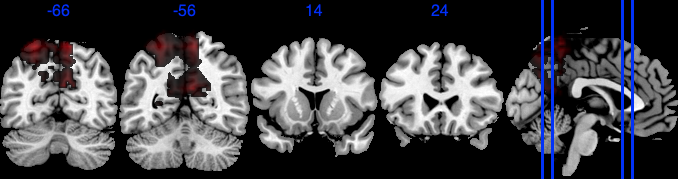

| Posterior inclusion probability (color range ) |

![]() |

| Positive posterior mean of the spatial mediation effects (color range ) |

| Negative posterior mean of the spatial mediation effects (color range ) |

We performed 100,000 iterations for the outcome model (1), discarding the first 50% as burn-in and thinning to retain 1,000 posterior samples. For the mediator model (2), we ran 40,000 iterations with a 30,000 burn-in, thinning every 10 iterations to obtain 1,000 posterior samples. Table 3 gives a summary of both the overall NIE and NDE and the top seven regions identified with the largest number of active voxels. The definition of NIE in each region is , where is the collection of all voxels in region . The rule for selecting the active voxels is based on cutting the posterior inclusion probability (PIP) at 50%, and the three regions with active voxels are reported in Table 3. Due to the very small effect sizes and low signal-to-noise ratio, we also include regions with voxels’ PIP greater than 10%. The posterior of NDE has a mean of 0.27 with the 95% credible interval . The posterior of NIE has a mean of 0.0885 with the 95% credible interval . The total effect of parental education level on general cognitive ability score is 0.36, with 95% credible interval (0.29,0.45). This suggests that parents with college degrees have a positive impact on children’s cognitive abilities, and about 25% of the effect is mediated through brain cognitive development. Figure 5 shows the estimated activation regions and the NIE in coronal view slides. Among the top identified activation regions, the most interesting is the left precuneus, which plays a key role in episodic memory, visuospatial processing, and self-consciousness (lou2004parietal; wallentin2006parallel). This region has been consistently implicated in cognitive processes related to memory retrieval and spatial awareness, which are crucial components of children’s cognitive development. In addition, other identified regions, such as the left inferior parietal region and the left postcentral gyrus, are associated with the interpretation of sensory information (radua2010neural; diguiseppi2023neuroanatomy). These regions are involved in integrating and processing sensory inputs, which are essential for tasks that require coordination between perception and cognition, such as working memory and executive function. These findings align with existing literature on the neural correlates of cognitive function, particularly in children. By identifying regions that have been consistently associated with cognitive processes, our results not only demonstrate the scientific validity of the BIMA approach but also provide meaningful insights into the brain areas that underlie cognitive abilities as captured by the ABCD study.